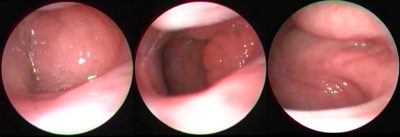

Çocuklarda sinüzit endoskopik muayene ile teşhis edilebilir. Bunun için günümüzde rontgen benzeri filmlere ihtiyaç duymuyoruz. ...